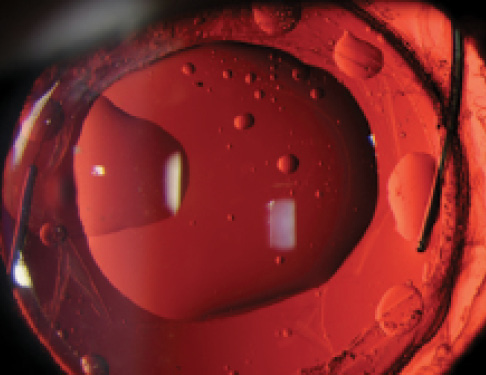

Figure 2. Clinical image showing a silicone IOL with silicone oil attachment. A posterior capsulotomy can also be seen.

Photo credit: James Gilman, CRA, FOPS, Moran Eye Center

Currently, IOL exchange is sometimes necessary when silicone oil droplets are stuck to the posterior surface of a silicone IOL after oil removal, as the droplets may be visually significant and we do not have a good way of removing them (Figure 2). Are you aware of safe techniques for removal of silicone oil droplets or calcium deposits that might obviate the need for IOL exchange?

Dr. Werner: For silicone oil attachment, studies have been done on some solutions or solvents such as F4H5, perfluorocarbon-perfluorohexyloctane (PFHO), and O44.6-9 Most of these studies were done in vitro, and it is not clear whether potential toxicity to intraocular structures was thoroughly investigated. It does not appear that use of these solvents entered clinical practice, at least not in any widespread manner.

Some authors suggest injecting an OVD to mechanically push the silicone oil droplets away from the visual axis.10